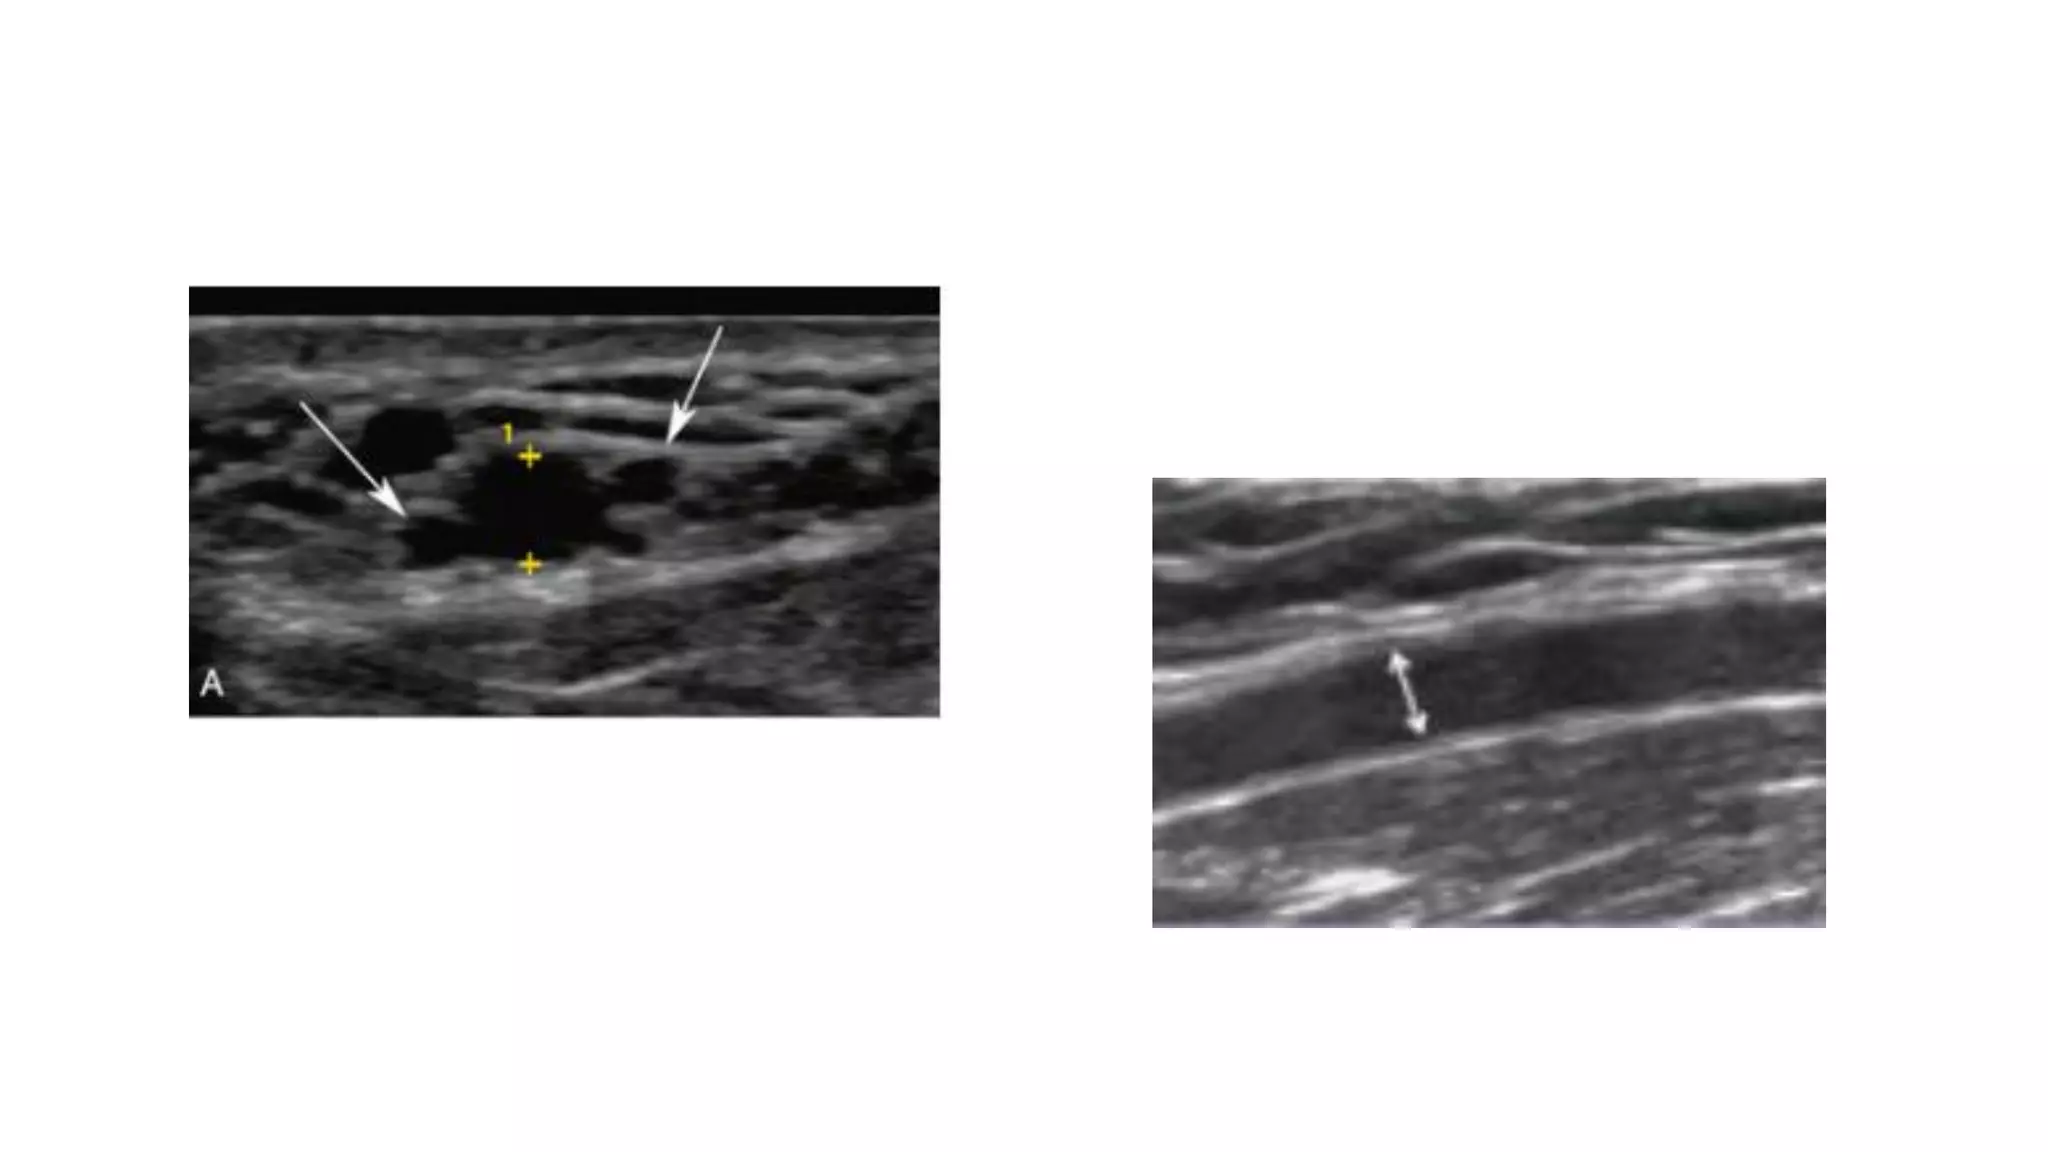

Ultrasound vascular mapping uses ultrasound to examine arteries and veins in the arms before dialysis access placement. It assesses vessel diameter, wall characteristics, blood flow, compressibility, and identifies the best vessels. The mapping examines arteries for internal diameter and wall appearance, uses Doppler to evaluate blood flow, and may check for calcification. It also assesses superficial arm veins for caliber, depth, wall appearance, distensibility, course, patency, and presence of collaterals to identify the best vessel options for dialysis access. A vein mapping worksheet is used to report the ultrasound findings.